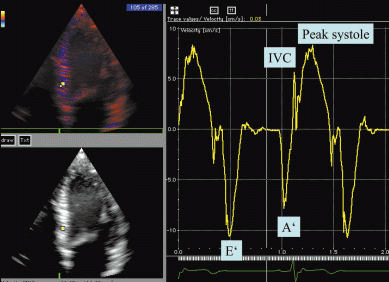

Eine diastolische Funktionsstörung kann mittels “Tissue doppler (Gewebedoppler)” zuverlässig erkannt werden. Auch Funktionsstörungen des linken Ventrikels können

hiermit deutlich besser ausgemessen werden.

Ergebnis einer Tissue-Doppler Untersuchung